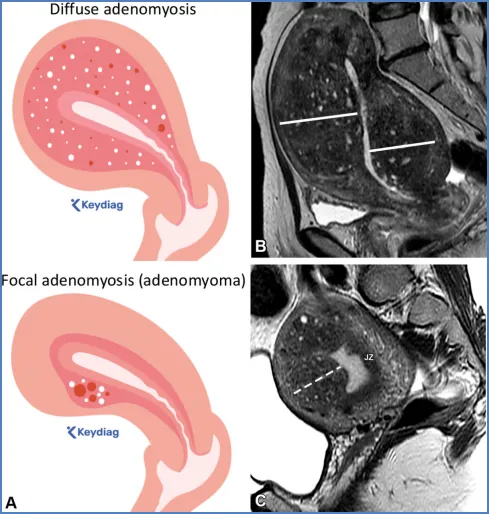

图2展示了女性盆腔MRI评估中常用的成像平面。经子宫的正中矢状面插图(A)显示了关键的MRI平面定位。A中的红线与子宫体平行,指示冠状斜位或卵巢轴的定位(如B中红线框所示),这有助于区分附件肿块的子宫起源和卵巢起源,并勾勒出子宫底的外轮廓,这在评估苗勒管畸形时具有重要意义。A中的黄线与子宫体垂直,显示子宫轴位斜平面的定位(如C中黄线框所示)。该平面用于评估子宫内膜癌分期中的肌层浸润深度,或显示子宫平滑肌瘤的位置。A中的灰线与宫颈垂直,代表宫颈轴位斜平面的定位(如D中灰线框所示),这对评估宫颈癌分期中的宫旁浸润至关重要。最后,A中位于膀胱颈水平的蓝色虚线将阴道分为上三分之二和下三分之一,这一区分对宫颈癌分期很重要。E=子宫内膜,iCS=宫颈内基质,JZ=交界区(子宫内肌层),oCS=宫颈外基质,OM=子宫外肌层,P=宫旁组织。图3,一名46岁女性患者在T2加权图像上子宫体和宫颈的正常表现。矢状位(A)、斜冠状位(B)、子宫斜轴位(C)、峡部斜轴位(D)和宫颈斜轴位(E)图像显示了子宫和宫颈的正常分区解剖结构。如A-C所示,位于中央的高信号子宫内膜(E)被低信号的结合带(JZ,即子宫内肌层)和中等信号强度的子宫外肌层(OM)所环绕。峡部标志着子宫颈连接处以及内口的位置,其特征为子宫外部轮廓变窄、宫颈管在通入子宫内膜腔之前呈漏斗状(A),以及子宫血管的入口(D中的箭头)。在矢状位T2加权图像(A)上,水平放置于膀胱颈的虚线将阴道的上三分之二与下三分之一区分开来,这一区分与宫颈癌分期相关。注意宫颈内的小纳博特囊肿(A、B和E中的箭头),以及左卵巢内的T2高信号卵泡(B中的*)。iCS=宫颈内间质,oCS=宫颈外间质,P=宫旁组织。教学要点:磁共振成像(MRI)能提供卓越的解剖学细节,多平面T2加权成像则是解剖学评估的基础。放射科医生必须透彻理解女性骨盆解剖结构,才能有效解读盆腔MRI。- 腹膜外间隙内有器官、肠系膜和结缔组织。腹腔内器官完全被腹膜包裹,而腹膜外器官则位于腹膜外间隙(图4)。

卵巢——卵巢是可活动的腹膜内器官,由卵巢韧带(连接卵巢与子宫角)、卵巢系膜(将卵巢固定于阔韧带)和悬韧带(连接卵巢与盆腔侧壁并包裹性腺血管)支撑(图6)(36)。性腺动脉起源于肾动脉下方的腹主动脉;右侧性腺静脉汇入下腔静脉,左侧性腺静脉汇入左肾静脉。性腺静脉直径大于0.8厘米为异常,尽管性腺静脉直径与静脉反流之间的相关性较差(37)。性腺血管走行于腰大肌前方、输尿管外侧。 卵巢的表现随月经周期阶段和绝经状态而变化。绝经前卵巢为较大的椭圆形结构,在T2加权成像上能清晰显示分区解剖结构,包括T2低信号的皮质、T2等信号的髓质(含疏松排列的基质和血管)、T2高信号的薄壁卵泡,偶尔可见黄体(19,38)。黄体因有黄素化的卵泡膜细胞而呈现T2等信号的厚壁,在退化过程中会变得锯齿状。非出血性黄体中央呈T1低信号、T2高信号,而出血性黄体中央呈T1和T2高信号,有时可见血细胞比容平面。静脉注射对比剂后,卵巢皮质和基质轻度强化,强化程度低于子宫肌层,而黄体壁则表现为早期明显强化(38)。绝经后卵巢比绝经前卵巢小,皮质和髓质呈T2等信号至低信号,偶尔可见小囊肿(38)。表S2以及图7-10详细描述了常见的生理性和其他良性卵巢表现的MRI特征(19,38-42)。图7. 两位不同患者的正常经前卵巢,突出显示了生理学观察结果。(A)示意图显示了带有卵泡的经前卵巢。(B)一位27岁女性患者的轴位T2加权图像显示一个椭圆形卵巢,具有T2低信号皮质(箭头)、T2等信号髓质(白色*)和多个T2高信号卵泡(黑色*)。(C、D)一位30岁女性患者的轴位T2加权(C)和对比增强脂肪抑制T1加权(D)图像显示了黄体(CL),这是经前女性常见的生理学表现。其影像学表现随发育阶段而变化。典型的黄体在T2加权成像上表现为囊性结构,中心呈高信号,壁厚且呈锯齿状,信号强度中等(C中的箭头),在静脉注射造影剂后明显强化(D中的箭头)。图8. 一名34岁闭经女性患者的多囊卵巢综合征与继发性非典型子宫内膜增生。(A)示意图展示了多囊卵巢,这是一种常见的内分泌疾病,影响高达10%的育龄女性。多囊卵巢综合征的诊断依据Rotterdam标准,该标准要求满足以下三项中的至少两项:多囊卵巢、月经稀发或无排卵,以及高雄激素血症。多囊卵巢的定义为:至少一侧卵巢的体积达到10毫升或以上,或者每个卵巢有20个或更多的卵泡(详见表S2)。(B)轴位T2加权图像显示双侧多囊卵巢增大,中央为T2等信号基质(小*),周围有多个T2高信号卵泡。(C)矢状位T2加权图像显示子宫内膜腔内呈不均匀的T2等信号(大*),对应活检证实的非典型子宫内膜增生。在所有增强后序列(包括延迟图像,未显示)中,非典型子宫内膜增生的强化程度低于子宫肌层,这与子宫内膜癌的强化模式相似。图9. 一名27岁女性患者的右侧卵巢扭转,该患者表现为急性盆腔疼痛。轴位T2加权图像显示右侧卵巢(RO)增大且水肿,伴有外周卵泡(箭头所示)。与正常的左侧卵巢(*)相比,右侧卵巢位置异常,位于子宫(U)的中央后方。卵巢扭转的其他表现(未显示)可能包括血管蒂扭转以及强化程度不一,这取决于缺血程度或是否存在梗死。图10. 一位43岁女性患者的输卵管卵巢脓肿,该患者在子宫内膜活检后出现恶心、呕吐和盆腔疼痛症状。轴位T2加权像(A)和对比增强脂肪抑制T1加权像(B)显示左侧附件区有一个多房囊性肿块。该肿块内含有脓性液体,在T2加权像上表现为不同的信号强度(A中的*),并具有增厚的强化壁以及多个强化分隔(B中的箭头)。高b值扩散加权像和ADC图(未显示)显示扩散受限,与脓液的存在相符。经皮引流后获得的细菌培养结果显示大肠杆菌阳性。——输卵管从子宫角延伸至卵巢(39)。近端的壁内部分穿过子宫肌层;远端带有伞端的漏斗部开口于卵巢附近的腹膜腔。输卵管被阔韧带的输卵管系膜包绕(图6)。在MRI上,它们表现为卵巢和子宫之间的T2低信号管状结构。子宫体和宫颈解剖。——子宫由子宫体和宫颈组成,宫颈下段(或子宫颈外口部)突入阴道上部(图2、3)(24、25、43)。在T2加权成像上,绝经前子宫的子宫体(子宫内膜、结合带和外肌层)和宫颈(宫颈管、宫颈内间质和宫颈外间质)均显示出清晰的分区解剖结构。绝经后或接受放射治疗后,这种分区解剖结构会变得不清晰(24、25、43)。子宫内膜腔由均匀的T2高信号子宫内膜衬里,延伸至同样为T2高信号的宫颈管(38)。子宫内膜厚度在子宫矢状面中部沿子宫长轴测量,其数值会随绝经状态和月经周期阶段而变化(表S3)(38、44-49)。对于有绝经后出血的患者,子宫内膜厚度≥5mm为异常;而无症状患者的阈值则不太明确(50)。结合带(子宫内肌层)呈T2低信号,向尾侧延续为T2低信号的宫颈内纤维间质。子宫外肌层呈T2等信号,过渡为宫颈外间质的T2等信号。正常结合带厚度≤8mm,若无微囊肿则可达11mm(45)。 子宫峡部是子宫体与宫颈之间的过渡区,在矢状位T2加权成像上表现为局限性缩窄,在轴位斜向T2加权成像上可见子宫血管进入(图2、3)(24、25)。宫颈内口和外口分别是宫颈管的上下开口。宫颈围绕宫颈管,包括上皮衬里和宫颈间质(43)。宫颈上段由腺状柱状上皮覆盖,宫颈下段(包括子宫颈外口部)由鳞状上皮覆盖。鳞状上皮与柱状上皮的交界处(鳞柱交界)在生育年龄具有动态变化,是大多数宫颈癌前病变和宫颈癌的起源部位。宫旁组织由主韧带和宫骶韧带构成,从宫颈两侧延伸至盆侧壁,包绕子宫血管、神经和输尿管(图2、3)。表S3以及图11-13概述了常见的子宫体和宫颈良性病变的MRI特征(38、44-49)。图11. 一位50岁女性患者的子宫内膜息肉,该患者在乳腺癌切除术后接受他莫昔芬治疗。(A)子宫矢状面示意图显示息肉状子宫内膜病变,伴有因子宫内膜腺体扩张而形成的囊性病灶。(B)冠状斜位T2加权像显示子宫内膜内有一个带蒂病变,具有T2低信号的纤维血管核心(白色箭头)和T2高信号病灶(黑色箭头),这些表现提示为子宫内膜息肉。通常可见明显的强化,与子宫肌层的强化程度相似(未显示)。明确诊断需要宫腔镜下切除,因为子宫内膜息肉、增生和肿瘤可能同时存在,且在影像学特征上可能重叠。偶然可见子宫腺肌症,表现为结合带内存在微囊肿(箭头所示)。图12. 弥漫性和局灶性子宫腺肌病(或子宫腺肌瘤)。(A)子宫矢状面中部的插图显示了弥漫性子宫腺肌病(上图)与局灶性子宫腺肌病或子宫腺肌瘤(下图)的对比。(B、C)两名不同的月经过多患者的矢状位T2加权图像显示,T2低信号的交界区(JZ)弥漫性增厚,伴有散在的T2高信号微囊肿(B中的实线),以及前部交界区伴有微囊肿的局灶性肿块样不对称增厚(C中的虚线)。这些表现是由于子宫肌层内存在异位子宫内膜腺体和间质(微囊肿)以及反应性平滑肌增生(交界区增厚)所致。图13. 纳博特囊肿与隧道簇。插图(A)及两名不同患者的子宫正中矢状面T2加权图像(B、C)显示,浅层宫颈基质内的单房囊肿为典型的纳博特囊肿(A图左图;B图),而向宫颈基质深部延伸的多房囊肿为隧道簇的特征性表现(A图右图;C图)。务必在增强图像上排除强化实性组织的存在(未显示),因为多房性宫颈病变中若出现强化实性组织,应怀疑宫颈胃型腺癌。可能需要进行宫颈锥形活检以明确诊断。子宫在骨盆内的位置会因膀胱充盈程度和盆腔瘢痕情况而有所不同。倾位指的是宫颈与阴道之间的角度:前倾位是向前倾斜,后倾位是向后倾斜(图14)(38)。屈曲描述的是子宫体与宫颈之间的角度:前屈是向前弯曲,后屈是向后弯曲(38)。图14. 插图(A)和磁共振图像(B、C)显示了女性骨盆内子宫的各种位置。子宫倾(Version)指的是宫颈与阴道之间的角度:A中的上组插图将该角度显示为黄线相对于红线的倾斜度。前倾(Anteversion)指向前倾斜,后倾(Retroversion)指向后倾斜。子宫屈(Flexion)描述的是子宫体与宫颈之间的角度:A中的下组插图将该角度显示为蓝线相对于黄线的倾斜度。前屈(Anteflexion)指向前弯曲,后屈(Retroflexion)指向后弯曲。两名患者的矢状位T2加权图像(B、C)中,B显示的是前倾前屈位子宫,C显示的是后倾后屈位子宫。阴道是一个纤维肌性结构,通过膀胱阴道隔与膀胱相隔,通过直肠阴道隔与直肠相隔(图4)(51)。在轴位T2加权成像上,绝经前阴道通常呈H形或W形塌陷,具有高信号的黏膜皱襞和低信号的壁。绝经后,皱襞消失,阴道壁厚度变薄。阴道上部有由突出的宫颈形成的穹窿,阴道下部通过阴道口开口于外阴前庭。表S4和图15详细描述了常见良性阴道病变的MRI特征(51-53)。图15. 四个不同患者的矢状面示意图(A)和轴位T2加权图像(B–E)显示了阴道囊肿、斯基恩氏腺囊肿以及尿道憩室。巴氏腺囊肿:位于耻骨联合处或其下方阴道后外侧壁的单房囊肿(A中的灰色椭圆形,B中的T2高信号囊性病变)。加特纳管囊肿:位于耻骨联合处或其上方阴道前外侧壁的单房囊肿(A中的蓝色椭圆形,C中的T2高信号囊性病变)。斯基恩氏腺囊肿:位于耻骨联合下方、阴道前方、尿道下段外侧的单侧或双侧小单房囊肿(A中的浅黄色椭圆形,D中的T2高信号囊性病变)。尿道憩室:在耻骨联合附近,尿道中远端后外侧出现的圆形、椭圆形或U形T2高信号液性囊袋状突起(A中的尿道囊袋状突起)。在罕见情况下,尿道憩室可能完全环绕尿道(E中的T2高信号环形囊性病变)。外阴由女性外生殖器组成(图16)(53)。阴阜位于耻骨联合前方,由脂肪组织构成。大阴唇是位于阴阜下方并与其相连的厚皮肤皱襞。小阴唇是大阴唇之间较薄的皱襞,向前会合于阴蒂头。小阴唇之间的前庭包含尿道外口(尿道口)和阴道口(阴道开口)。图16. 示意图(A)和轴位T2加权图像(B)显示了外阴区域或女性外生殖器。阴阜位于耻骨联合前方,由脂肪组织构成。大阴唇是位于阴阜下方且与其相连的厚皮肤皱襞。小阴唇是大阴唇之间较薄的皱襞,向前汇聚于阴蒂头。小阴唇之间的前庭前部有尿道外口(尿道口),后部有阴道口(阴道开口)。参考文献:https://doi.org/10.1148/rg.250029